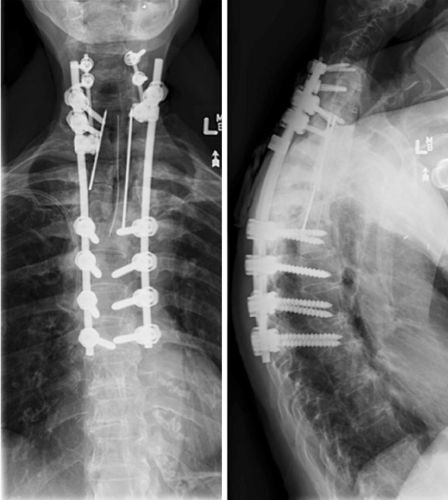

脊柱初次术后13年随访站立位胸椎x线